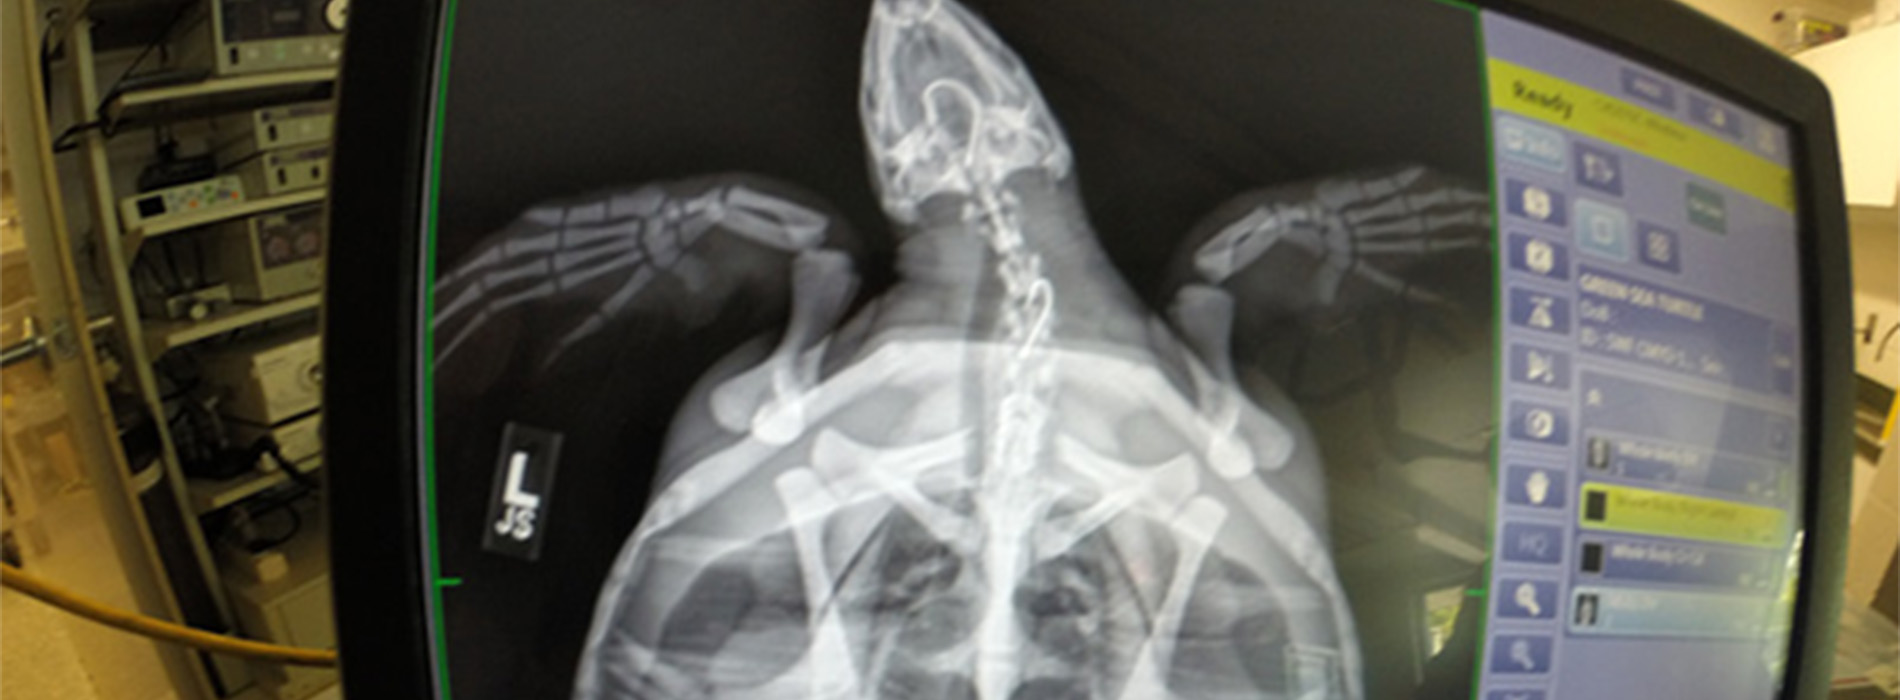

The surgical suite may include an x-ray machine, anesthesia equipment, a respirator unit, an ultrasound machine, and a surgery table.

Veterinarians sometimes also use specialized diagnostic equipment such as ultrasound machines and endoscopy equipment (scopes for seeing inside an animal's body).